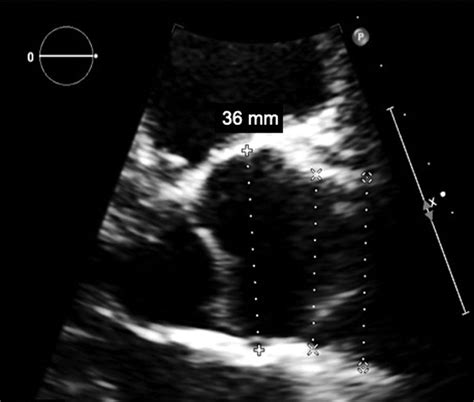

researchgate.net

TEE detection of a PFO. (a) The left PFO height and P…

544×460